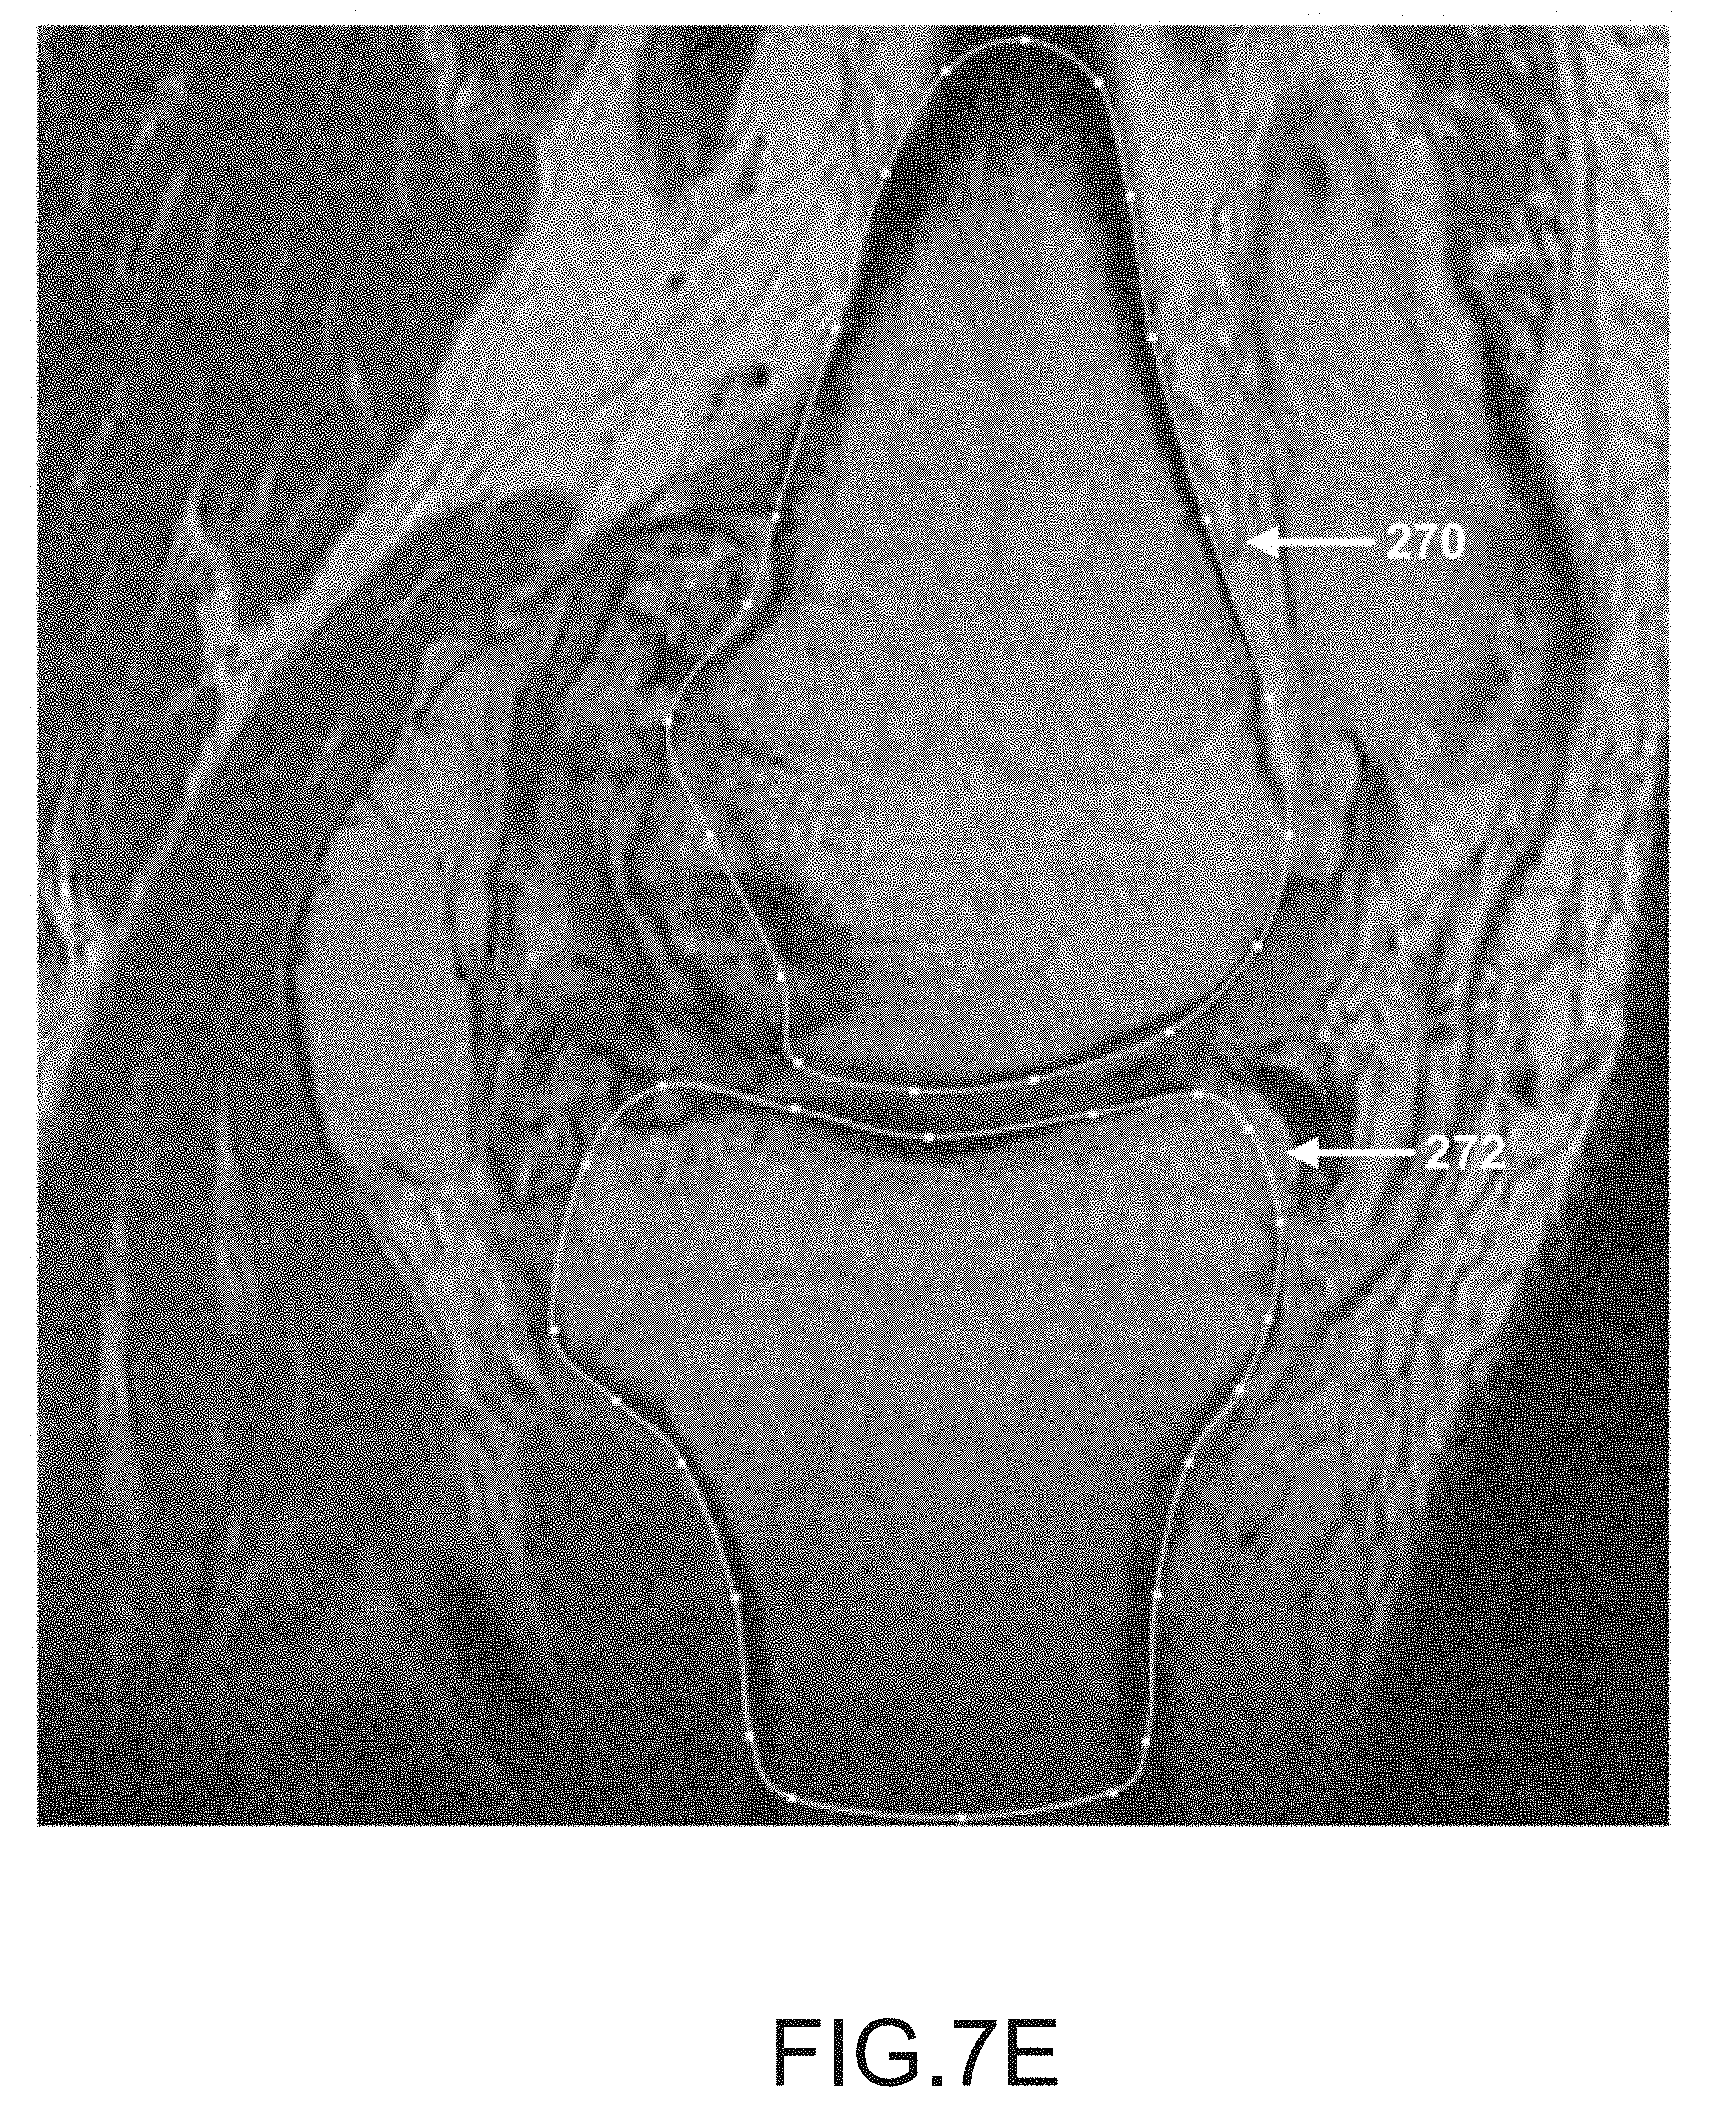

FIG. 7E is another sagittal plane image slice of a segmented femur and tibia.

After operation 250 obtains scan data (e.g., scan images 16) generated by imager 8, operation 252 may be performed to segment the femur data of the scan data. During this operation, the femur may be located and spline curves 270 may be generated to outline the femur shape or contour lines in the scan slices, as depicted in FIGS. 7A-7K. It should be appreciated that one or more spline curves may be generated in each slice to outline the femur contour depending on the shape and curvature of the femur as well as the femur orientation relative to the slice direction.

After operation 256, operation 258 may be performed to segment the tibia data in the scan data. During this operation, the tibia is located and spline curves may be generated to locate and outline the shape of the tibia found in the scan slices, as depicted by tibia spline curves 272 in FIGS. 7A-7K. It should be appreciated that one or more spline curves may be generated in each slice to outline the tibia depending on the shape and curvature of the tibia as well as the tibia orientation relative to the slice direction.